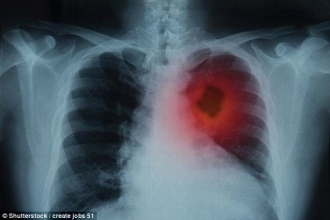

据英国《每日邮报》报道,专家已开发出一种网络计算器,该计算器可预测人们患肺癌的风险,且准确率接近90%。可减少因不必要的CT扫描而受到辐射的人数,并最大限度地识别真正有风险的人。

全球数据显示,每年有160万人死于肺癌。这种疾病每年都会导致全球数百万人死亡。但其中很多人并不是高风险人群。专家已经开发出一种在线工具,可以计算出你患肺癌的风险。这也是第一个能够准确预测轻度吸烟者,年轻人以及多年前戒烟患者肺癌的模型。

有关该检测的发现称为亨特肺癌风险模型,已发表在《E生物医学》杂志上。领导这项研究的是特伦德拉、格莱旺厄尔医院的高级肿瘤学家Oluf Dimitri R e博士,发现该测试接近88%准确。来自克里特大学的R e博士及其同事警告说,使用小剂量辐射的CT扫描不仅昂贵,对身体也有一定的伤害。研究人员希望,这些发现能让医生减少对他们认为有肺癌风险的吸烟者进行CT扫描。